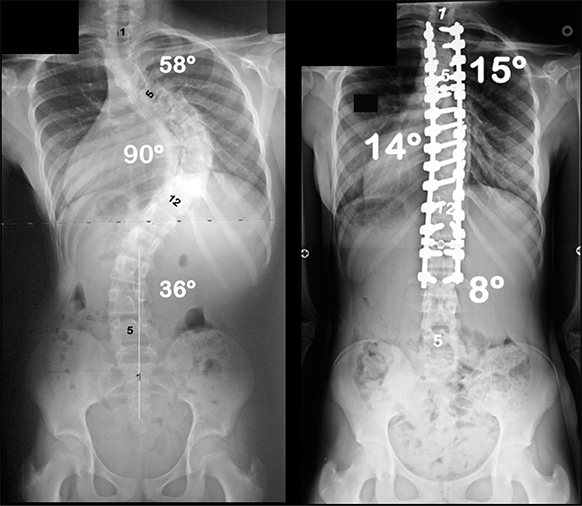

After meeting eight surgeons who could not treat her severe scoliosis, Patricia almost gave up hope of living without pain. But, the team at NewYork-Presbyterian didn’t hesitate—they performed reconstruction and fusion to straighten her spine and heal her nerves, giving her the hope that nobody else could.